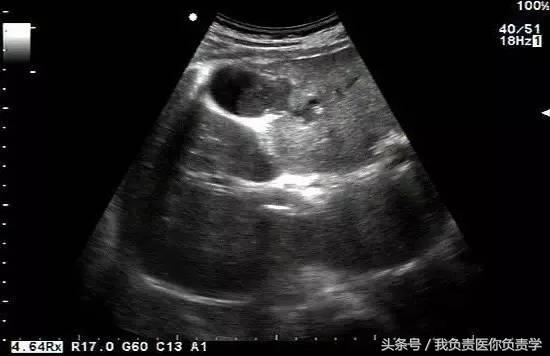

图1示胆囊体积明显增大,内部透声差

图2示胆囊周围可见液性暗区分布

图3-图6示胆囊壁局部回声中断,探头加压及松开时CDFI可见红色及蓝色多普勒信号